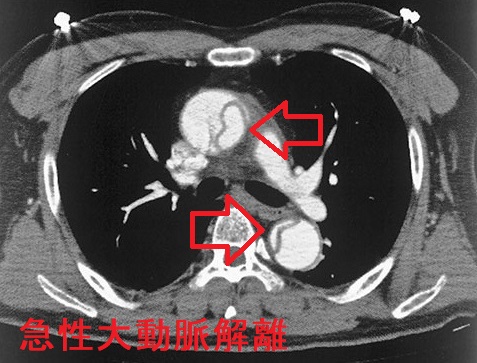

甲状腺機能低下症/潜在性甲状腺機能低下症/橋本病で動脈硬化が進行、急性大動脈解離とDIC・心タンポナーデ、腹部大動脈瘤、甲状腺動脈瘤破裂おこる。急性大動脈解離は血中Dダイマー上昇。A型上行大動脈解離が大動脈基部に及ぶと心臓栄養する冠状動脈入口部を圧迫、急性心筋梗塞と同じ心電図所見に。B型解離(DeBakey III)で主要分枝を含まない領域に限局は降圧治療のみ。甲状腺動脈瘤は血栓塞栓症なく、高率に破裂し死亡率20%のため無症候性でもコイル塞栓術、外科的切除。動脈硬化進行してできる腹部大動脈瘤は破裂すると突然死。通常、無症状で破裂始まると腹痛・腰痛。

急性大動脈解離とは、大動脈壁の脆弱さ、動脈硬化、高血圧などが原因で、血管内膜に亀裂が入り、中膜が裂け、内腔側が内膜フラップ(intimal flap)になって、その下に偽腔が生じる病態です。

急性大動脈解離は、大動脈から分枝する動脈が巻き込まれて様々な症状を伴います。

- 心タンポナーデ(死因の一位)、心筋梗塞、大動脈弁閉鎖不全症(AR)(下記)

Stanford B型急性大動脈解離(DeBakey III)で主要分枝を含まない領域に限局している場合は降圧治療のみ(降圧目標は収縮期血圧105~120mmHg、β遮断薬が第一選択)。